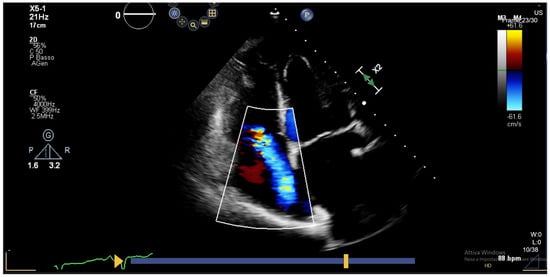

- Tona, F.; Caforio, A.L.; Montisci, R.; Angelini, A.; Ruscazio, M.; Gambino, A.; Ramondo, A.; Thiene, G.; Gerosa, G.; Iliceto, S. Coronary flow reserve by contrast-enhanced echocardiography: A new noninvasive diagnostic tool for cardiac allograft vasculopathy. Am. J. Transplant. 2006, 6 Pt 1, 998–1003. [Google Scholar] [CrossRef] [PubMed]

- Tona, F.; Osto, E.; Tarantini, G.; Gambino, A.; Cavallin, F.; Feltrin, G.; Montisci, R.; Caforio, A.L.; Gerosa, G.; Iliceto, S. Coronary flow reserve by transthoracic echocardiography predicts epicardial intimal thickening in cardiac allograft vasculopathy. Am. J. Transplant. 2010, 10, 1668–1676. [Google Scholar] [CrossRef] [PubMed]

- Sade, L.E.; Eroğlu, S.; Yüce, D.; Bircan, A.; Pirat, B.; Sezgin, A.; Aydınalp, A.; Müderrisoğlu, H. Follow-up of heart transplant recipients with serial echocardiographic coronary flow reserve and dobutamine stress echocardiography to detect cardiac allograft vasculopathy. J. Am. Soc. Echocardiogr. 2014, 27, 531–539. [Google Scholar] [CrossRef] [PubMed]

- Pichel, I.Á.; Fernández Cimadevilla, O.C.; de la Hera Galarza, J.M.; Pasanisi, E.; Ruiz, J.M.G.; Molina, B.D.; Rodriguez, J.L.L.; Sicari, R.; Fernández, M.M. Usefulness of dual imaging stress echocardiography for the diagnosis of coronary allograft vasculopathy in heart transplant recipients. Int. J. Cardiol. 2019, 296, 109–112. [Google Scholar] [CrossRef] [PubMed]

- Bjerre, K.P.; Clemmensen, T.S.; Poulsen, S.H.; Hvas, A.M.; Løgstrup, B.B.; Grove, E.L.; Flyvholm, F.; Kristensen, S.D.; Eiskjær, H. Coronary Flow Velocity Reserve and Myocardial Deformation Predict Long-Term Outcomes in Heart Transplant Recipients. J. Am. Soc. Echocardiogr. 2021, 34, 1294–1302. [Google Scholar] [CrossRef] [PubMed]